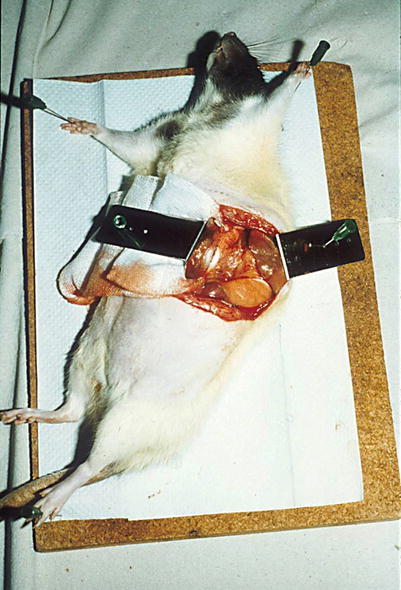

Under general anesthesia, the rat, with an optimal weight of about 250 g, is fixed lying on the back. The abdomen is opened via an incision beneath the left costal margin or a midline incision. The intestine together with the spleen is rotated to the right side and fixed with broad hooks (Fig. 2.1). With the help of two Q-tips, which are rotated in contrary direction, the aorta is exposed.

Fig. 2.1

Rat weighting around 250 g, the intestine together with the spleen is rotated to the right side and fixed with broad hooks; the left side of aorta is exposed